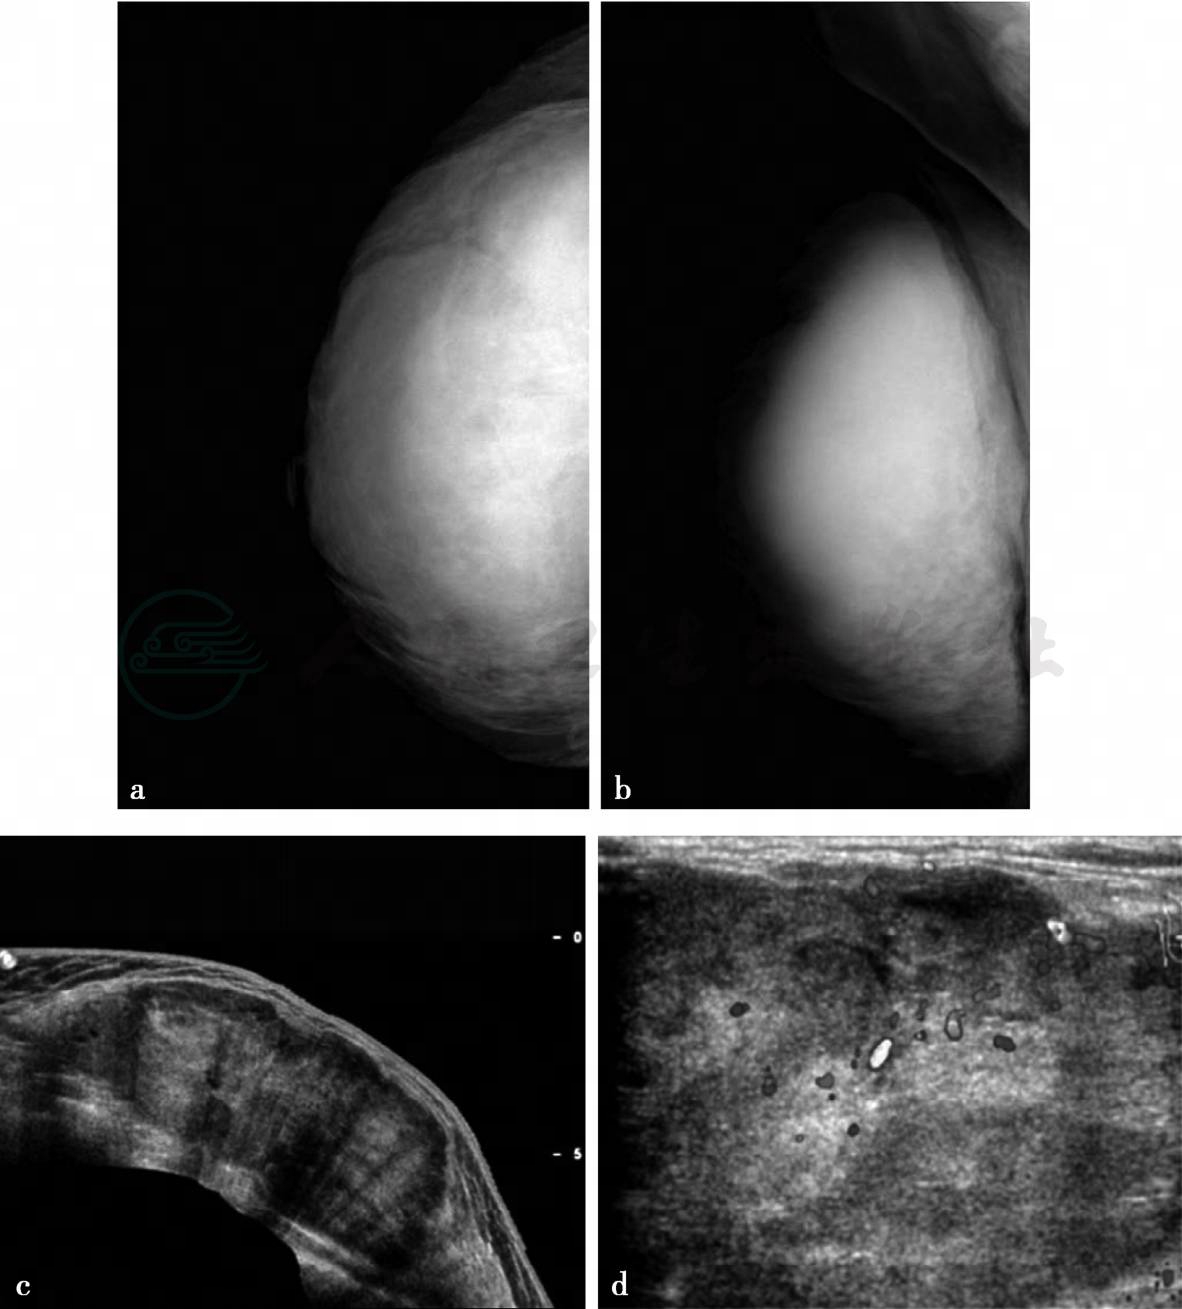

X线、超声及彩色多普勒血流图。

图1 图1a,X线影像头尾位(CC位)。图1b,X线影像内外斜位(MLO位)。X线显示右乳巨大肿块,边缘清楚,密度尚均匀,未见恶性钙化,邻近皮下脂肪层变薄,皮肤不厚。图1c,超声检查纵切面图,超声示右乳巨大低回声肿块,内部回声不均,其内见不规则囊状间隙。图1d,彩色多普勒血流图,周围及其内见丰富血流信号